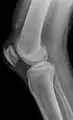

| An x-ray demonstrating quadriceps tendon rupture. Note the abnormal angle of the patella and soft-tissue swelling marked by the arrow. | |